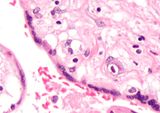

Micrograph of CMV placentitis.